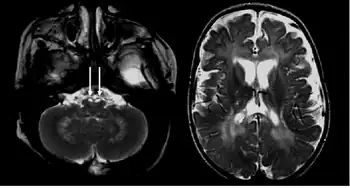

Symptoms in asymptomatic infantile-onset (<12 months after birth) and later-onset Krabbe disease present themselves differently. Of individuals with infantile-onset Krabbe disease, 85–90% display progressive neurologic deterioration in infancy and death before the age of two.[6] Symptoms include irritability, fevers, limb stiffness, seizures, feeding difficulties (like GERD), vomiting, staring episodes, and slowing of mental and motor development. In the first stages of the disease, doctors often mistake the symptoms for those of cerebral palsy. Other symptoms include muscle weakness, spasticity, deafness, optic atrophy, optic nerve enlargement,[7] blindness, paralysis, and difficulty when swallowing. Prolonged weight loss may also occur.

The buildup of unmetabolized lipids adversely affects the growth of the nerve's protective myelin sheath (the covering that insulates many nerves) resulting in demyelination and severe progressive degeneration of motor skills. As part of a group of disorders known as leukodystrophies, Krabbe disease results from the imperfect growth and development of myelin.

There are a few ways to help pinpoint the presence of Krabbe disease. Newborn screening for Krabbe disease includes assaying dried blood cells for GALC enzyme activity and molecular analysis for evidence of GALC enzyme mutations. Infants displaying low enzyme activity and/or enzyme mutations should be referred for additional diagnostic testing and neurological examination.[11] 0-5% GALC enzyme activity is observed in all symptomatic individuals with Krabbe disease.[6] High concentration of psychosine in dried blood spots may also be identified as a marker for Krabbe disease.[12] A 2011 study discovered that individuals with Krabbe disease, more so in later-onset individuals, tend to have an abnormal increase in CSF protein concentration.[13]

The disease may be diagnosed by its characteristic grouping of certain cells (multinucleated globoid cells), nerve demyelination and degeneration, and destruction of brain cells. Special stains for myelin (e.g., luxol fast blue) may be used to aid diagnosis.